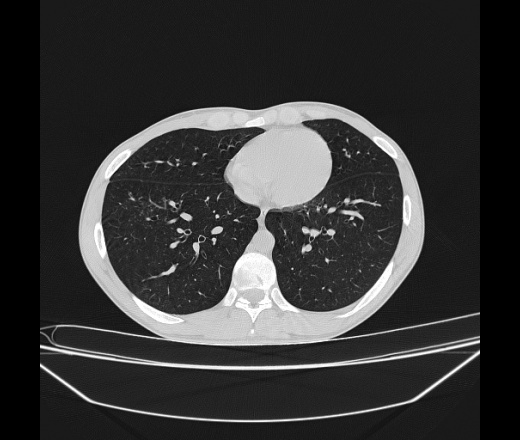

Молодой парень 18 лет, призывник, при прохождении ФЛС на верхушек левого легкого выявили очаги средней интснисвности с нечеткими контурами, тяжи. Сделали бок и томограммы 6-7-8. Везде описывают как очаговый твс. Вижу только перибронхиальный фиброз. Что за изменения в бронхах, указано нижи стрелками, тоже перибронхиальный?

Не стал бы говорить об очагах. Акцентировал бы не на фиброзе, а на тракционных бронхоэктазах. Не обязательно они результат tbc бронхов, но проверить не помешает.

Иван, пациент ведь уже "направлен с ОПТД", так?surprise Возвращайте его назад с заключением о возможном микобактериозе. Остаточные поствоспалительные ( посттуберкулёзные?) в дифряд.Очаговый твс с неясной активностью они уже себе "нарисовали", как я поняла.

+1 за микобактериоз.